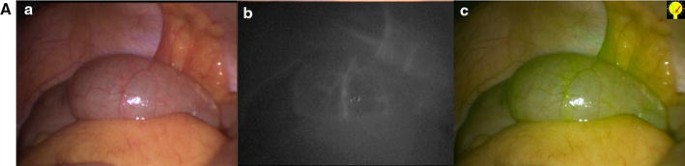

NIR perfusion assessment in laparoscopic right hemicolectomy. a Normal light. b Near-infrared fluorescence. c Superposition of NIR and normal light in green. A Intraoperative photos showing a clear demarcation line after vessel division. B Ileotransverse anastomosis before IDC injection, showing no fluorescence. C Perfusion assessment of the ileotransverse anastomosis